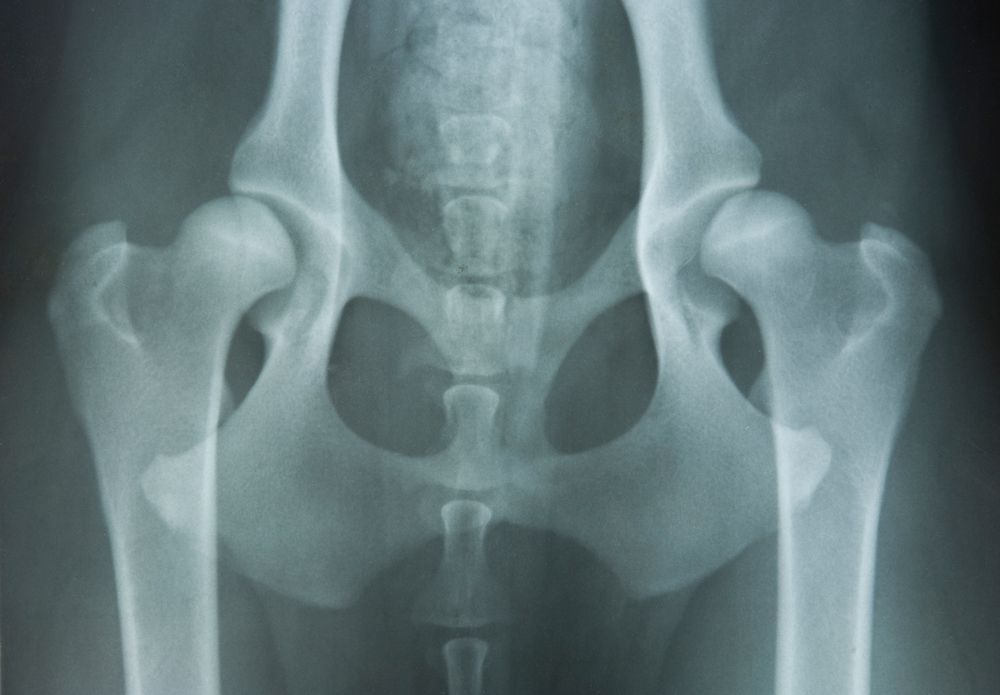

Casing the Joint

What you need to know about hip dysplasia